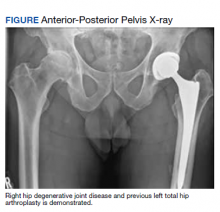

A 61-year-old male patient presented with progressive right hip pain. At age 37, he had a left THA via a PA due to hip dysplasia and a revision on the same hip at age 55 (the polyethylene liner was replaced and the cobalt chromium head was changed to ceramic), again through a PA. An orthopedic clinical evaluation and X-rays confirmed end-stage DJD of the right hip (Figure). He was informed to return to plan an elective THA when the “bad days were significantly greater than the good days” and/or when his functionality or quality of life was unacceptable. The orthopedic surgeon favored an MPA but offered a hand-off to colleagues who preferred the DAA. The patient was given information to review.